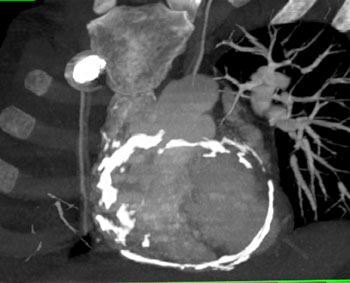

Question 6: 50ish yr old male with increasing SOB and dyspnea.What’s the diagnosis?

Diagnosis: Angiosarcoma of the Pericardium

• Most common cardiac sarcoma

• Most common in middle aged men

• Most commonly located near right atrial free wall with involvement of pericardium

• Typically infiltrates pericardium

• Normal thickness under 2 mm

• Calcification may be a sign of constrictive pericarditis